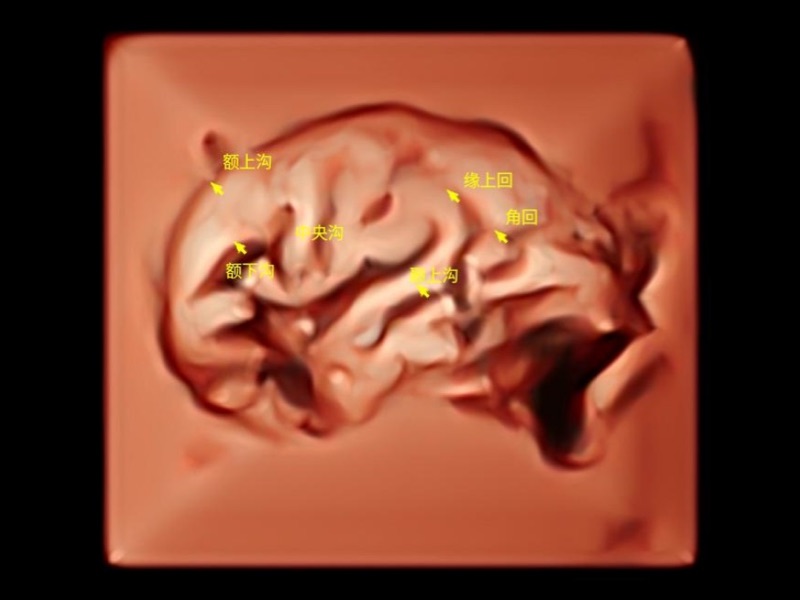

作為開(kāi)立醫(yī)療全新打造的超高端旗艦超聲產(chǎn)品,從探頭抬起喚醒開(kāi)啟掃查到多維探頭發(fā)射接收,通過(guò)先進(jìn)的場(chǎng)成像發(fā)射、自適應(yīng)聚合重建等技術(shù),基于RF Data原始射頻數(shù)據(jù)在圖像生成、高端功能等方面實(shí)現(xiàn)突破,為婦產(chǎn)科、兒科提供全方位臨床解決方案。